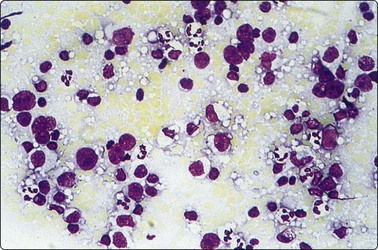

Plasmacytoma (Figs 5.35, 5.36)9,69,146,147

Usually in middle aged or elderly patients. Commonly involve bones, upper airways and only rarely lymph nodes.9,71

image

Fig. 5.35 Plasmacytoma

Pure population of well-differentiated plasma cells (MGG, HP).

Fig. 5.36 Myeloma in lymph node

Poorly differentiated plasma cells. This patient had multiple myeloma (Pap, HP).

Criteria for diagnosis

1 cells resembling mature or immature (nucleoli-containing) plasma cells,

2 eccentric nuclei, condensed chromatin or blastic-like, condensed cytoplasm,

3 immunophenotype: CD38, CD79a, CD138, OCT-2, CIg; CD 20 and Pax 5 very often negative,

4 aberrant immunophenotype: CD56, CD10, CD117, cyclin D1.

Be wary of unusual cellular morphology, e.g. occasional cases dominated by pleomorphic, signet ring, clear and sarcomatoid cells, which may be difficult to recognize as plasma cells. The rare variant with a small lymphocyte-like morphology may mimic a B-cell lymphoma.